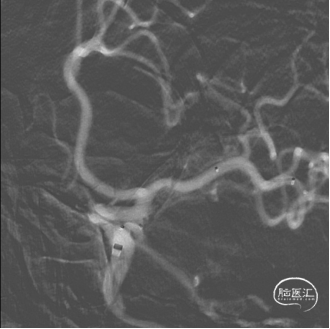

术前影像

术前CT

造影所见:双侧颈动脉血管稍迂曲僵硬,双侧后交通动脉开放,左侧颈内动脉后交通段可见一“囊状”突起,大小约6.19mm*4.07mm*2.35mm,瘤颈4.03mm,基底宽,边缘不光整,有两个子瘤,指向后下方,后交通动脉从瘤颈处发出。

造影

3D